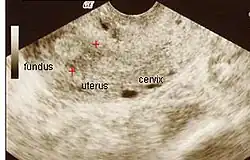

| Ultrasound view. | |

The history of a pregnancy event followed by a D&C leading to secondary amenorrhea or hypomenorrhea is typical. Hysteroscopy is the gold standard for diagnosis.[18] Imaging by sonohysterography or hysterosalpingography will reveal the extent of the scar formation. Ultrasound is not a reliable method of diagnosing Asherman's Syndrome. Hormone studies show normal levels consistent with reproductive function.